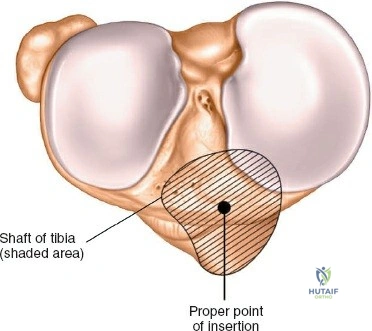

- Proximal Tibia: The preferred entry point for tibial nails lies in the proximal tibia, typically between the anterior tibial spine and the lateral edge of the patellar tendon. The infrapatellar fat pad (Hoffa's fat pad) must be navigated. Careful attention to the articular surface is paramount to avoid iatrogenic damage to the tibial plateau. The patellar tendon can be split or approached paratendinously, with long-term studies showing no significant difference in knee pain.

The incision should be adequate to allow clear access to the entry point and accommodate the targeting jig. The patellar tendon can be carefully split longitudinally or approached paramedially (medial or lateral to the tendon). - Entry Point Determination: The ideal entry point is crucial for proper nail alignment and preventing iatrogenic damage. It is typically located on the anterior cortex of the tibia, just medial to the lateral edge of the patellar tendon, distal to the articular surface of the tibial plateau.

- Fluoroscopic Guidance: Use an Awl or K-wire under AP and lateral fluoroscopy to confirm the entry point. The AP view should show the wire positioned to align with the central axis of the medullary canal. The lateral view should show the wire in line with the anterior cortex, avoiding a posterior entry which can damage the posterior cortex and lead to malalignment.